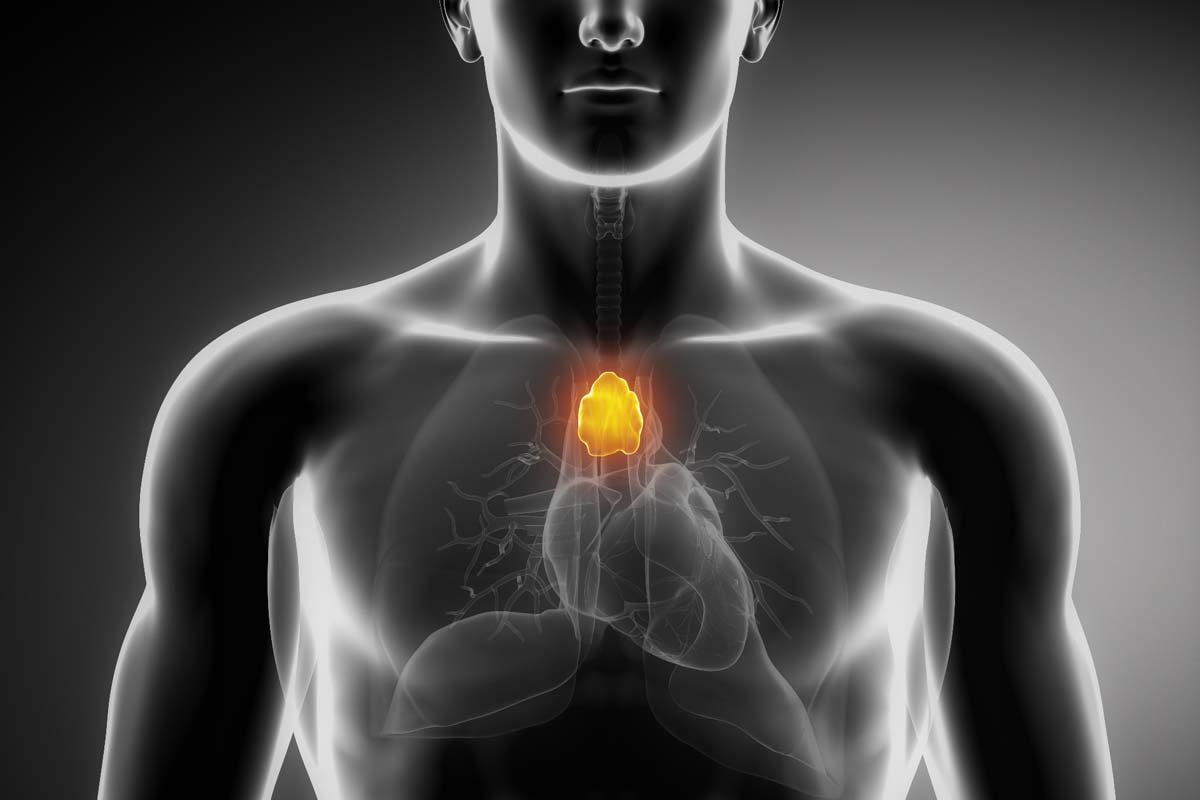

Что такое тимома?

Тимома представляет собой опухоль тимуса, и хотя это одна из наиболее редко встречающихся опухолей медиастина (пространства в грудной клетке между легкими), её значение не может быть уменьшено. Сама по себе опухоль может быть доброкачественной или злокачественной.

Тимус, или вилочковая железа, — это орган, играющий ключевую роль в развитии иммунной системы человека, особенно в детском возрасте. Расположен он в грудной клетке, непосредственно за грудиным и между легкими. В детском возрасте тимус активно функционирует, но с возрастом его активность уменьшается, и он постепенно заменяется жировой тканью.